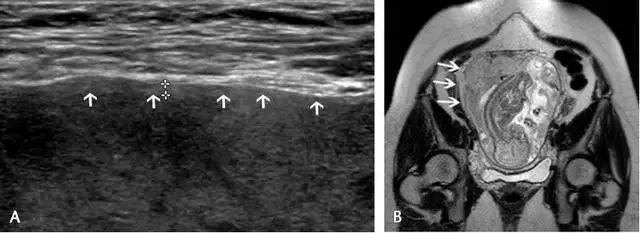

超声最早可在孕 6 周(经阴道超声)或孕 10 周(经腹部超声)显示出胎盘,表现为妊娠囊周围的薄层环状高回声。妊娠 12~13 周时,多普勒超声可显示绒毛血流。孕 14~15 周时,胎盘已充分发育,表现为显著的高回声。此时,也可看到由蜕膜、肌壁、子宫血管等组成的胎盘后复合体(图 1)。

中孕时,胎盘逐渐成熟变大,表现为更加均质的高回声(图 2),其内可有边界欠清的低回声区,为胎盘湖。晚孕时,多普勒超声可显示胎盘内的丰富血流。

图 1 孕 12 周时的正常胎盘矢状面,其后可见低回声的胎盘复合体(小箭头)

图 2 孕 24 周时的正常胎盘横切面,显示胎盘的回声、厚度及其后方的低回声肌壁(箭头)